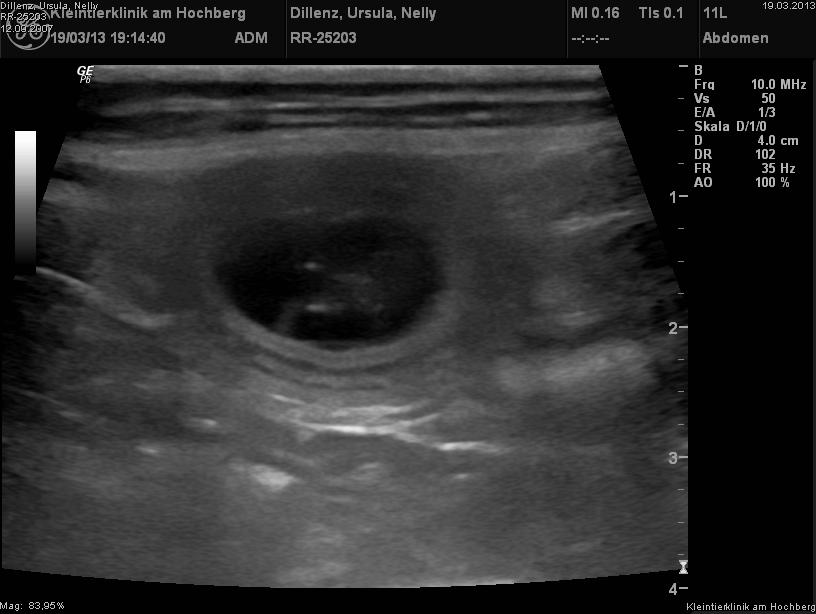

Ultraschallbild vom 19.3.2013